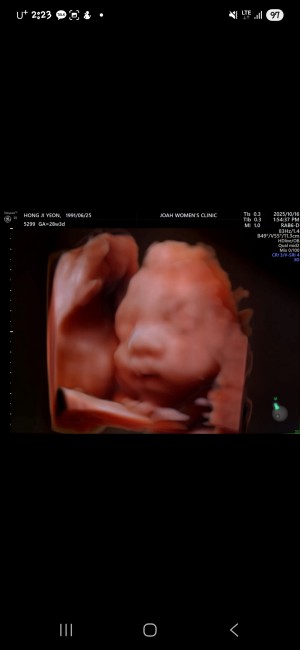

30주 입체초음파입니다 :)

이레IYRAE

2025-08-21